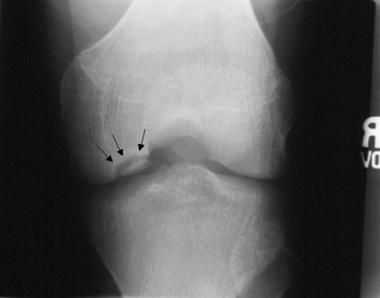

Клинически и рентгенологически в течении болезни Кенига различают две стадии. Первая стадия протекает обычно скрыто, без видимых проявлений, по типу неясного артрита без рентгенологических проявлений. Местно возникает отечность коленного сустава, боли неясной локализации. Только при диспансерном наблюдении за больным и периодическом рентгеновском контроле можно видеть в медиальном мыщелке бедренной кости появление поверхностно расположенного очага просветления. Очаг разрушения имеет ровные контуры. Постепенно этот очаг отторгается в виде свободно лежащего тела.

В дальнейшем эта стадия прерывается незначительной травмой и происходит выпадение свободного тела и ущемление его в суставе. Для второй стадии болезни Кенига характерны резкие боли в суставе, блокады сустава. Жидкость в суставе определяется редко, что отличает ее от блокады сустава при ущемлении поврежденного мениска. Рентгенологически во второй стадии ниша бывает пустой, а выпавшее тело из медиального мыщелка бедренной кости обнаруживается в полости коленого сустава.